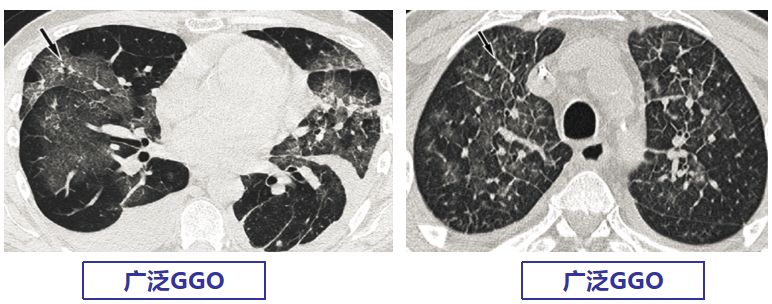

CMV肺炎的影像学可表现为以下几种:

小叶中央性结节、随机或淋巴管周围分布结节、广泛磨玻璃影、气腔实变、叶间隔增厚。其中小叶中央性结节 (69%)、双肺GGO(69%)、气腔实变(54%)最为常见。

【图4】文献报道的巨细胞病毒肺炎常见影像表现